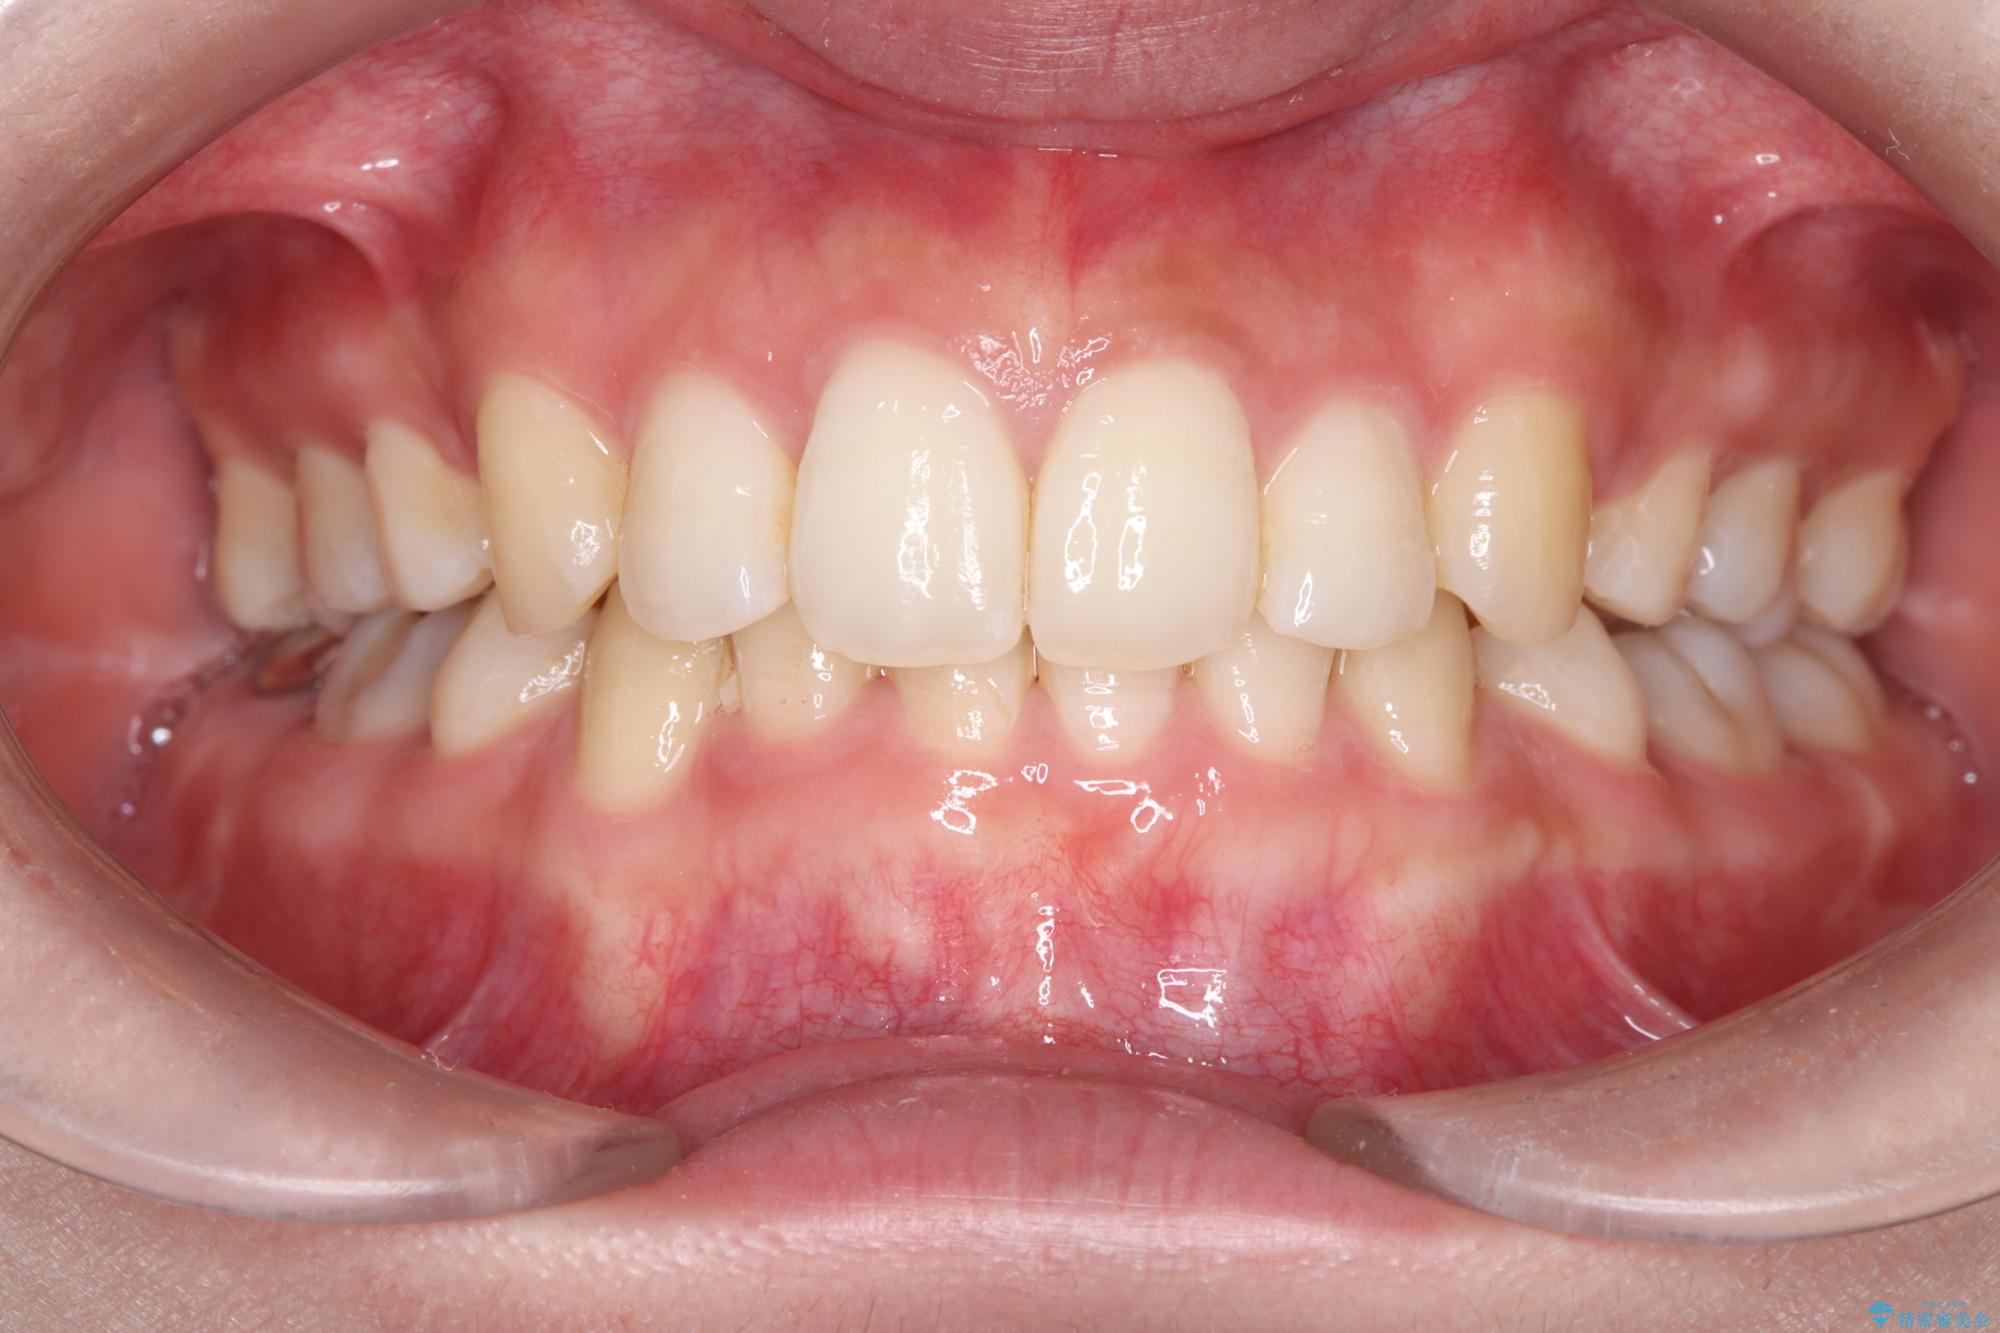

- 前歯から奥歯にかけて歯の重なりが激しい歯のがたつき(重度叢生)を主訴にご来院されました。精密検査の結果、歯が並ぶスペースが大幅に不足しており、歯並びを整え、口元を美しく引っ込めるためには、スペースの確保が必要と診断しました。そこで、上下左右の第一小臼歯(4番目の歯)を計4本抜歯し、そのスペースを利用して歯並び全体を整える抜歯矯正の治療計画を立案。装置には、透明で目立たないインビザラインを採用し、審美性と治療効果の両立を目指しました。

今回の治療では、重度の叢生を改善するため、まず計画通り上下左右4本の小臼歯を抜歯し、歯を並べるための十分なスペースを確保しました。装置には透明で取り外し可能なインビザラインを使用。抜歯によってできたスペースを最大限に活用し、マウスピースを定期的に交換しながら、デコボコを解消しつつ、前歯を効果的に後退させました。

治療の結果、長年の悩みであった重度の歯のがたつきが解消され、口元の突出感も改善。機能的にも安定し、審美的にも美しい、理想的な歯並びを獲得していただけました。